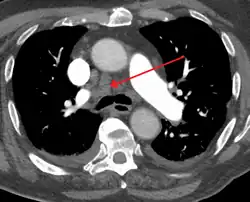

Mediastinal adenopathy

Widened mediastinum

Widened mediastinum in a patient with achalasia

Widened mediastinum/mediastinal widening is where the mediastinum has a width greater than 6 cm on an upright PA chest X-ray or 8 cm on supine AP chest film.[11]

A widened mediastinum can be indicative of several pathologies:[12][13]